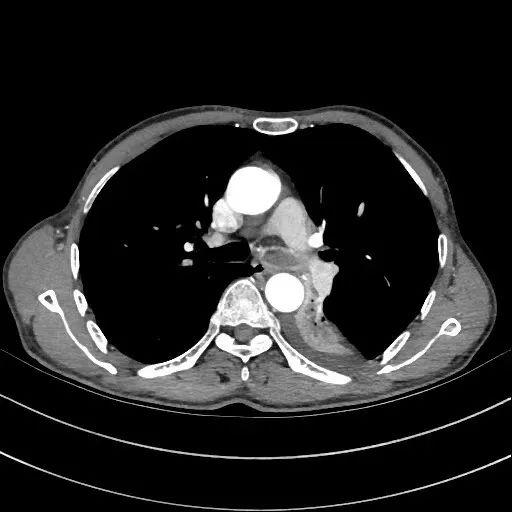

吴某入院后,医生为其做了胸部CT,检查提示肺部新生物,并且新生物侵入左主支气管,几乎将管腔堵塞。为迅速改善症状及明确诊断,呼吸内镜介入团队为吴大爷做了第一次气管镜下介入治疗,术后确诊为肺肉瘤。

两周后,吴某如约再次入院,按照计划择期安排了支气管镜介入治疗。但这次住院后,医生发现吴大爷的气短症状又较半个月前加重了,稍微活动后就有窒息感,在吸氧3L/min的情况下,指脉氧仅仅维持在90%的临界线上。而陈晖副主任医师查房中发现,吴某呈典型的喘息貌,左肺呼吸音完全消失,并且胸部CT影像中,左主支气管已经被新生物完全堵塞,左肺下叶已完全不张。

左主支气管几乎完全堵塞

肿物向右侧侵犯

术中,陈晖发现患者的左主支气管新生物已经将管腔堵塞得严严实实,距上一次住院短短两周的时间里,肿物明显迅速生长了很多。镜下直观到的情景更严峻、更不容乐观,巨大的新生物已经向右侧侵犯,随时可能将右主支气管也堵住。